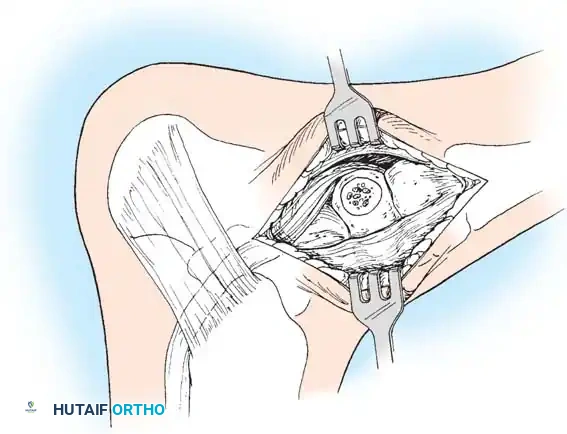

جراحة إزالة التحام الكاحل والعقب

تُجرى هذه العملية عادة للمرضى الأصغر سناً (10 إلى 15 عاماً) عندما يكون الالتحام في المفصل الأوسط (Middle Facet) صغيراً (أقل من 50% من مساحة المفصل) ولا توجد علامات على خشونة المفاصل.

يتم الدخول جراحياً من الجهة الداخلية للقدم، ويتم استئصال الجسر العظمي بدقة باستخدام أدوات دقيقة حتى يظهر الغضروف السليم للمفصل. كما هو الحال في الالتحام السابق، يتم وضع نسيج دهني أو شمع عظمي لمنع الالتصاق مجدداً.

جراحة دمج المفاصل

جراحة دمج المفاصل (Arthrodesis) هي الحل الجذري والنهائي للحالات المتقدمة، وتُستخدم عادة للبالغين، أو في الحالات التي يكون فيها الالتحام العظمي كبيراً جداً، أو عند وجود خشونة (تهتك غضروفي) واضحة في مفاصل القدم، أو في حال فشل جراحات إزالة الالتحام السابقة.

* الدمج الثلاثي (Triple Arthrodesis): يتم فيه دمج ثلاثة مفاصل رئيسية في الجزء الخلفي من القدم وتثبيتها بمسامير طبية لتلتحم كعظمة واحدة. يزيل هذا الإجراء الألم تماماً ويصحح شكل القدم، ولكنه يلغي الحركة في هذه المفاصل.

* دمج المفصل تحت الكاحل (Subtalar Arthrodesis): دمج مفصل واحد فقط إذا كانت الخشونة مقتصرة عليه.